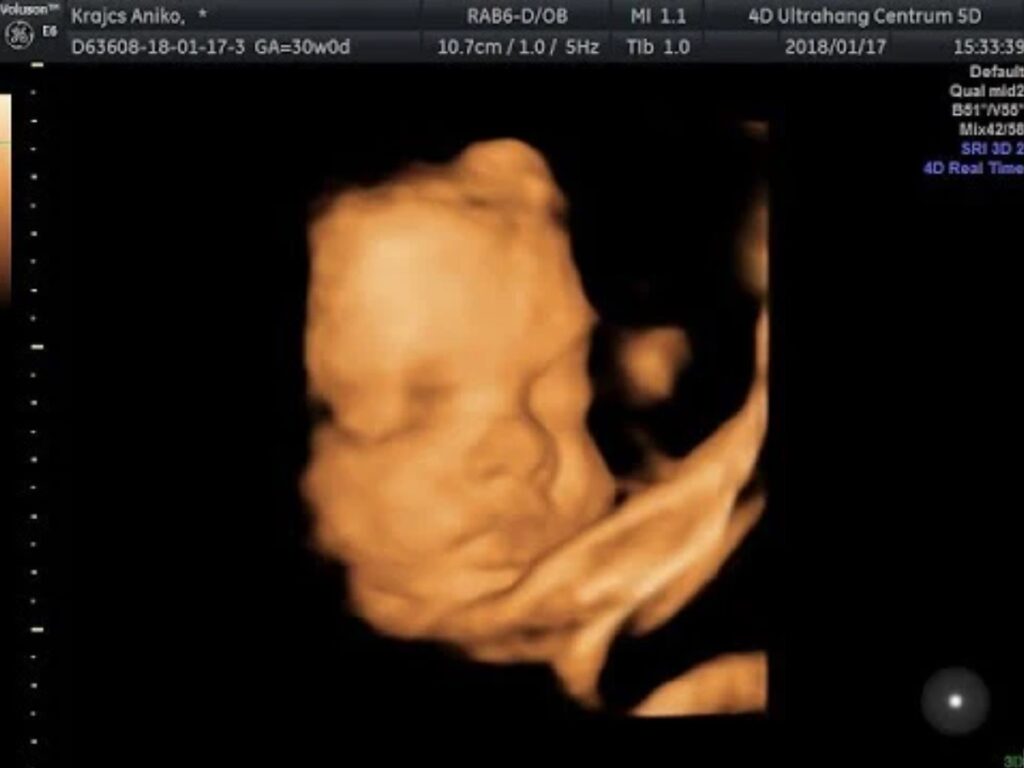

Bebek artık bu haftada yaklaşık olarak 40 cm’e ulaştı. Ağırlığı ise ortalama 1300 gram civarındadır.

Bebek bu dönemde artık doğmaya hazır olduğunu hissettirir. Akciğerleri dışında hemen hemen her şeyi oluşmuştur. Kaşları, kirpikleri, saçları artık iyice son şeklini almıştır. El ve ayaklarını da her zamankinden daha çok oynatır.